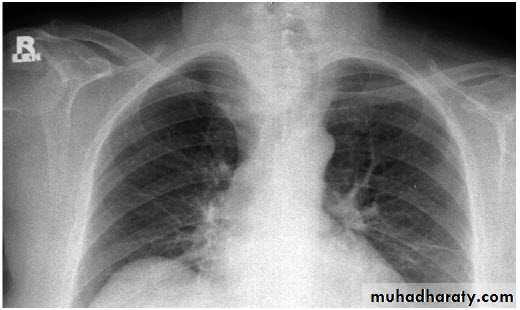

Hilar enlargement ( Bilateral )

1) Expiratory film2)LAP –hematological malignancy(leukemia, lymphoma ..)

-infections ( whooping cough or TB ?)

3) Vascular causes

Hilar enlargement ( unilateral )

1)Apparent –rotation-scoliosis

2) LAP